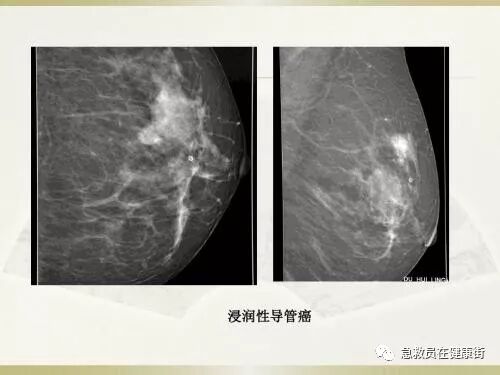

图9-61 “山峰”样浸润性导管癌细胞碎片

浸润性导管癌由山峰状三角形细胞碎片(A)构成,这与良性的小管形似山峰(B)相似或相关,可能由扩张的小管增生而成,浸润性导管癌中缺乏肌上皮细胞,细胞体积增大、排列上密集重叠。Pap×200、400